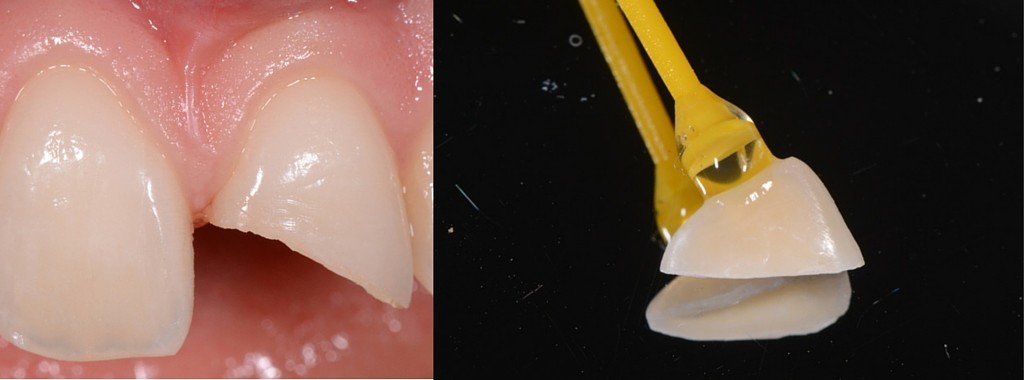

Essayage du morceau fracturé